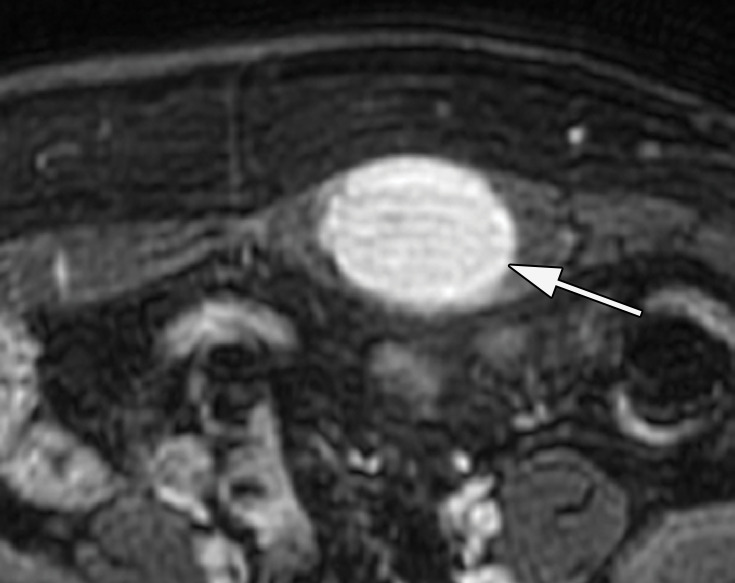

Figure 15a.

Desmoid tumor in the abdominal wall of a 35-year-old woman, which was confirmed on the basis of percutaneous biopsy. (a) Axial CT image shows a hyperenhancing abdominal wall mass centered in the left rectus sheath (arrow). (b–d) Axial nonenhanced T1-weighted MR images show a hypointense mass. After administration of a gadolinium contrast agent, there is progressive homogeneous enhancement of the mass (arrow in b–d) on sequential arterial phase (c), portal venous phase (not shown), and delayed phase (d) images. (e) US image shows a hypovascular hypoechoic mass (arrow).

Figure 15b.

Figure 15c.

Figure 15d.

Figure 15e.